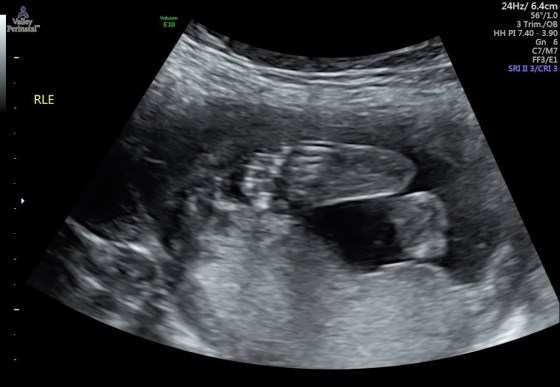

And last but not least, pictures of baby brother! Isn’t he already cute??